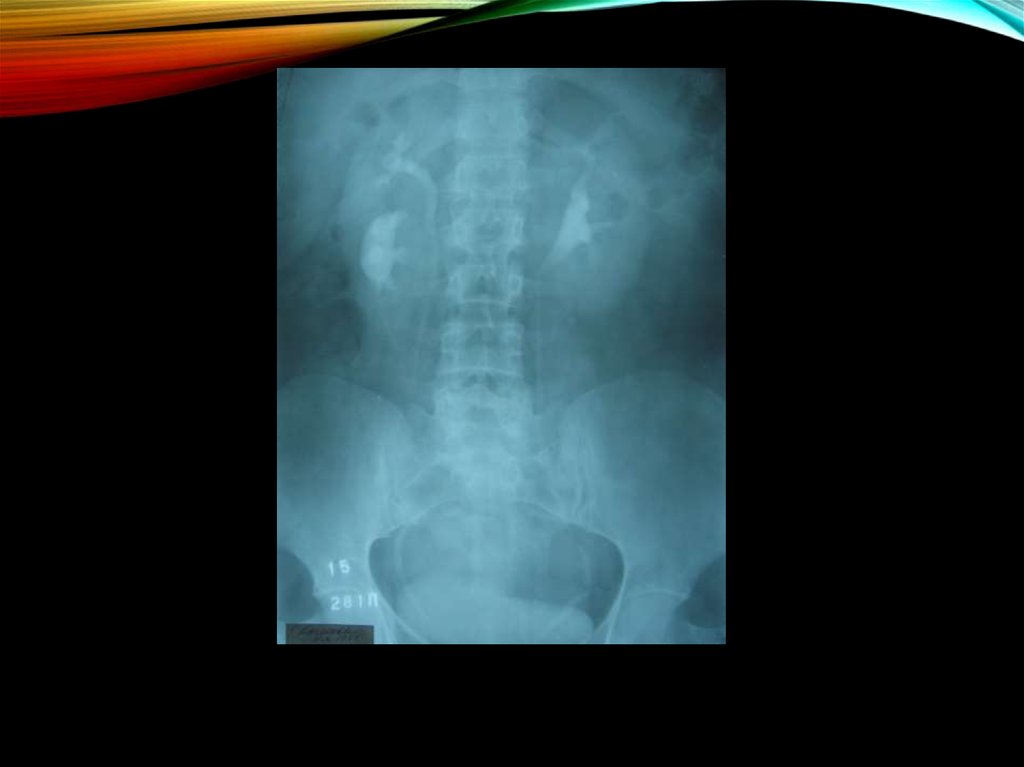

19. Изменения рентгенологической картины:

ИЗМЕНЕНИЯ РЕНТГЕНОЛОГИЧЕСКОЙ

КАРТИНЫ:

экскреторная урография

снижение тонуса верхних мочевых путей

уплощенность и закругленность углов форниксов

сужение и вытянутость чашечек

позднее - деформация чашечек, сближение их

пиелоренальные рефлюксы

пиелоэктазии

асимметрия размеров почек

ретроградная пиелография:

картина гипоплазированной почки;

почечная ангиография (в редких случаях):

уменьшается просвет почечной артерии

периферическое кровоснабжение обедняется

облитерируются мелкие сосуды коркового

вещества.